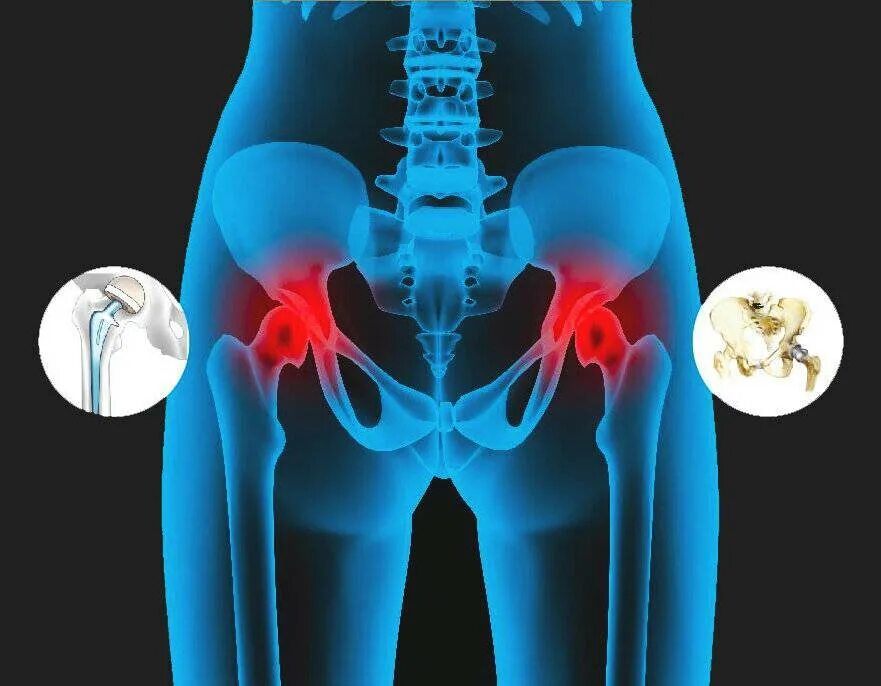

Можно ли лечить тазобедренный сустав